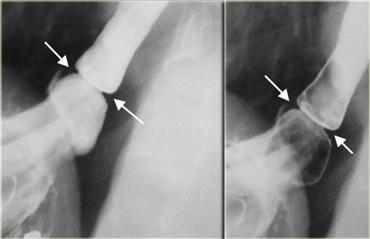

Bên trái là hình ảnh của một nam giới 52 tuổi không có triệu chứng.

Hình chiếu thẳng (AP) và hình chiếu nghiêng cho thấy màng mỏng, ngắn (mũi tên) với mức độ nhô vào lòng ống tối thiểu.

Bên trái là hình ảnh của một phụ nữ 42 tuổi bị khó nuốt do màng thực quản.

Lòng ống bị hẹp > 50%